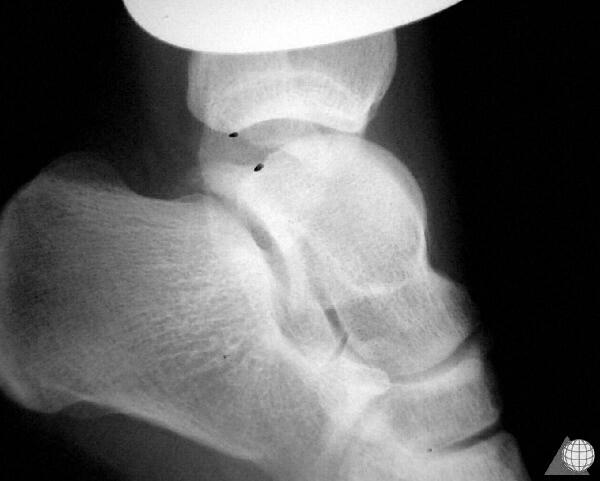

After reviewing key anatomic and pathologic features of ankle sprains, Dr. Fournier shares that the physical exam for lateral ankle sprains is most ideal 4 to 5 days after initial injury. She says that this timing, in her experience, allows for the exam, including stress maneuvers, to have less impact from edema and guarding, making it more precise and reliable. She goes on to review best practices in imaging and diagnostics.